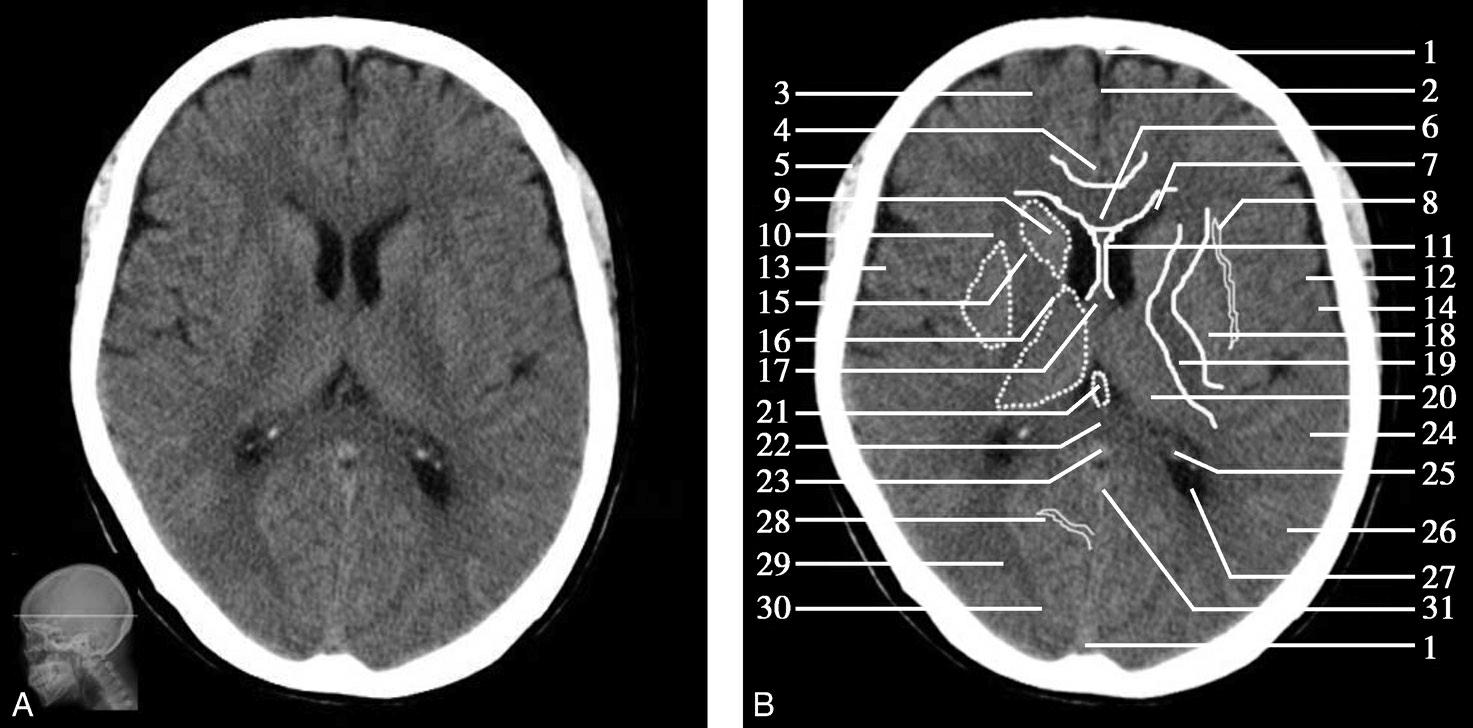

图1-2-29 基底节层面

A.横断面;B.横断面标注

1.上矢状窦;2.大脑镰;3.额叶;4.扣带回;5.颞肌;6.胼胝体膝部;7.侧脑室前角;8.岛叶;9.尾状核头部;10.外囊;11.透明隔;12.中央沟;13.中央前回;14.中央后回;15.内囊前肢;16.内囊膝部;17.穹窿柱;18.豆状核;19.内囊后肢;20.丘脑;21.大脑内静脉;22.胼胝体压部;23.大脑大静脉;24.颞叶;25.脉络膜丛;26.顶叶;27.侧脑室三角区;28.顶枕沟;29.视辐射;30.枕叶;31.直窦

图1-2-31 脑叶划分示意图

T.颞叶;F.额叶;O.枕叶;I.岛叶;P.顶叶

双侧侧脑室前角呈倒“八”字形向前外方伸展,其前壁为胼胝体膝部、内侧壁为透明隔、外侧壁为尾状核头。透明隔后方与穹窿柱相连,穹窿柱与两侧背侧丘脑前部间为室间孔,沟通双侧侧脑室及第三脑室。第三脑室居双侧背侧丘脑间,呈纵向走行的裂隙状。尾状核头与背侧丘脑的外侧为“> <”形的内囊,由前肢、膝及后肢三部分组成,内囊与额盖、顶盖之间,由内侧向外侧依次为豆状核、外囊、屏状核、最外囊、岛叶及外侧裂。枕叶与顶叶分界为顶枕沟,此沟在胼胝体压部层面显示最佳。胼胝体压部外侧有侧脑室三角区,内有脉络丛,常见钙化。大脑半球内侧面前部可见额内侧回和扣带回,后部可见扣带回和舌回。

顶枕沟位于胼胝体之后,是半球内侧面的一条较深的沟,此沟后方及大脑镰两侧为枕叶,为顶枕叶的分界标志。外侧裂池位于半球凸面的中点处,并向内、向后延伸,可作为额、颞叶的分界标志。此层面同时出现大脑半球的额、颞、顶、枕4个叶。

基底节为脑卒中的好发部位,与纹状动脉的解剖特点有关,深穿支动脉的破裂和栓塞可分别引起基底节区的出血和梗死(图1-2-32、图1-2-33)。